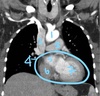

What is a CT scan?

Basically a 3-D X-Ray

The source and detector rotate around the patient, and the image is reconstructed by a computer

What are 4 “pros” of a CT scan?

- Better tissue resolution than X-Ray

- Fast

- Widely available

- Can reconstruct the image in infinite planes

What are 2 “cons” of a CT scan?

- Much more ionizing radiation than X-ray (~1 year of background radiation)

- Contrast dye can cause renal failure